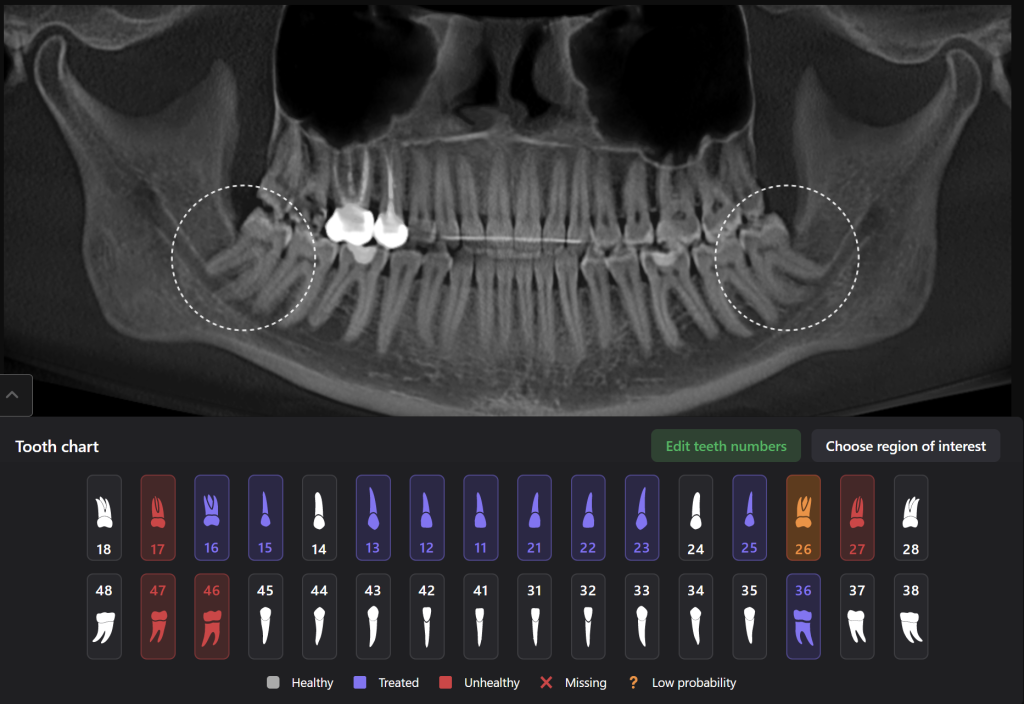

Diagnocat AI will help you carefully plan your procedure, such as the removal of teeth 38 (Universal 17) and 48 (Universal 32), minimizing the risk of possible complications

The 3D reconstruction from CBCT data (STL report Diagnocat) is a convenient tool for determining the level of complexity of the upcoming surgical procedure

It also serves as a visualization tool during communication with the patient